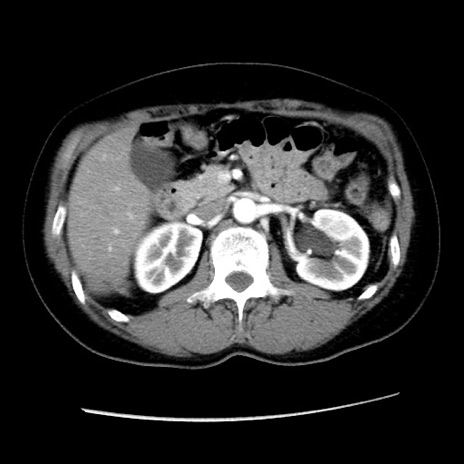

症例10(横断像)

【症例】 50歳代女性

【主訴】 腹痛

【現病歴】前日生レバーを食べた。今朝に排便あり。 昼前に突然発症の腹痛を生じ、当院救急外来を受診した。

【既往歴】 子宮筋腫にてで子宮全摘後

【身体所見】 意識清明、腹部:平坦、軟、下腹部やや左を中心に圧痛・反跳痛あり、筋性防御あり

【データ】WBC 7800、CRP 0.07